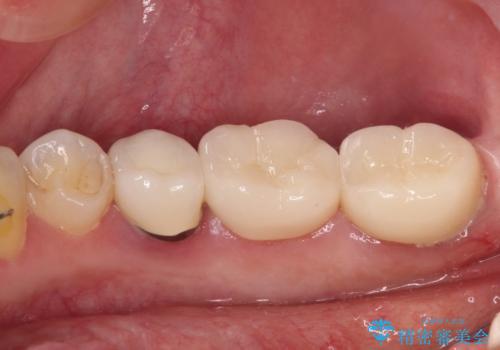

歯とクラウンの適合が良くなることで、食事の度にしみるという症状はなくなり、歯間部にものが挟まって不快な思いをすることもなくなりました。